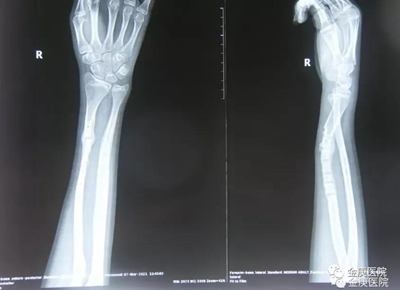

這個(gè)病例在院長(zhǎng)宋兆普41年從醫(yī)生涯中,是很普通的一例。在2020年8月,鄭州市的一位14歲少年,玩耍時(shí)不慎將右手的尺骨和橈骨同時(shí)骨折,鄭州一家大醫(yī)院實(shí)施切開(kāi)復(fù)位鋼板固定術(shù),六個(gè)月后取出鋼板。沒(méi)有多長(zhǎng)時(shí)間,原骨折部位突然出現(xiàn)血腫,經(jīng)檢查橈骨再次骨折,尺骨愈合畸型。手術(shù)需要將畸形愈合的部位,再次斷開(kāi)重新復(fù)位,畸形愈合的部位已長(zhǎng)出骨痂,而且尺骨本身細(xì),首次實(shí)施內(nèi)固定時(shí),留有許多螺絲孔,在檢查片上清晰可見(jiàn),脆弱的部位多,如果使用外力斷開(kāi)復(fù)位,可能會(huì)使尺骨其他部位骨折,家長(zhǎng)多方咨詢沒(méi)有醫(yī)院肯接收治療。

2021年3月,患者家長(zhǎng)慕名帶孩子來(lái)到金庚醫(yī)院找到了院長(zhǎng)宋兆普,他在外科專家徐發(fā)亮等配合下,只用了短短5分鐘時(shí)間,在不切口的情況下,完美將患者畸形尺骨斷開(kāi),而后又將橈骨與尺骨同時(shí)復(fù)位。從醫(yī)學(xué)檢查片看,對(duì)位可,手術(shù)成功,術(shù)后進(jìn)行外夾板固定,配合服用活血通絡(luò)和生骨接骨的院內(nèi)制劑,42天后,通過(guò)醫(yī)學(xué)檢查完全康復(fù)。

14歲少年正骨前